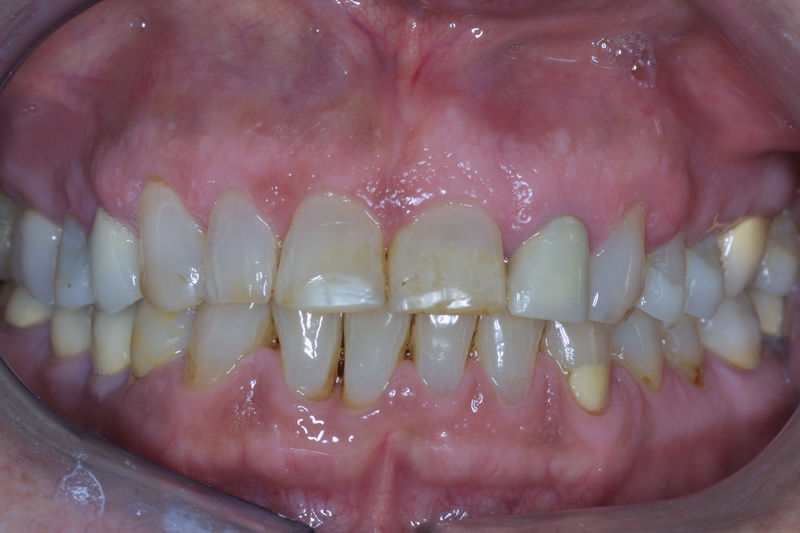

Implantes, ortodoncia y coronas.